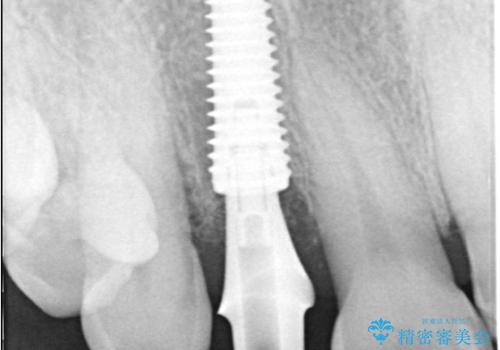

インプラント治療は、低侵襲で短期間に行える「抜歯即時インプラント治療」を選択しました。

この方法は、抜歯したその日にインプラントを埋入し、手術が1回で済むのが大きな特徴です。

治療期間も短く、抜歯からわずか3か月でオールセラミッククラウンを装着することができます。